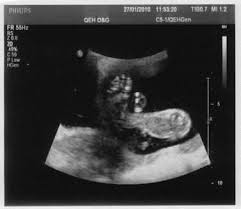

Que significa lf en un ultrasonido. Se consideró como biometría fetal estándar a la medición del diámetro biparietal DBP circunferencia cefálica CC longitud del fémur LF y circunferencia abdominal CA. CC en español corresponde al perímetro de la cabeza siempre en milímetros. EPF en español estimación del peso del feto en gramos.

Mide la longitud del fémur el hueso del muslo y se expresa en milímetros. Por sunnyfunny Mié Oct 08 2008 859 pm. LF en español es longitud del fémur expresada en milímetros.

Que significa dbp en. Permite establecer la fecha aproximada de la concepción y la fecha probable del parto. SEGUNDO TRIMESTRE 14 a 28 semanas En el segundo trimestre al igual que en el tercero se aceptan como mínimos requerimientos para cálculo de la edad gestacional la medición de DBP CA CC LF.

COLUMNA CORAZON DE 4 CAMARAS. Y biometría fetal secundaria a la medición del diámetro cerebeloso transverso DCT longitud renal LR y longitud del pie LP. Diámetro biparietal de un lado a otro de la cabeza expresado en milímetros.

Ultrasonido de diagnóstico es una técnica de diagnóstico no invasiva que se utiliza para producir imágenes dentro del cuerpo. Que significa cc en un ultrasonido. CRL Diámetro Biparietal Longitud del Fémur Circunferencia Abdominal Edad Gestacional etc. El perímetro abdominal del bebé expresado en milímetros. Aproximadamente la longitud del feto es 7 veces mayor que la del fémur. EPF en español estimación del peso del feto en gramos. Es la fecha estimada del parto.